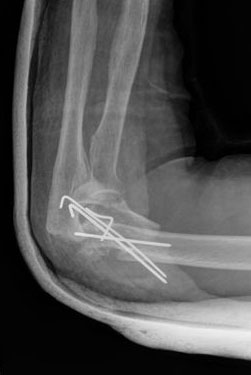

Fractura supracondílea de codo.

Fractura supracondílea de codo.Tras reducción y osteosíntesis.

Fractura supracondílea de codo. Tratamiento con agujas.